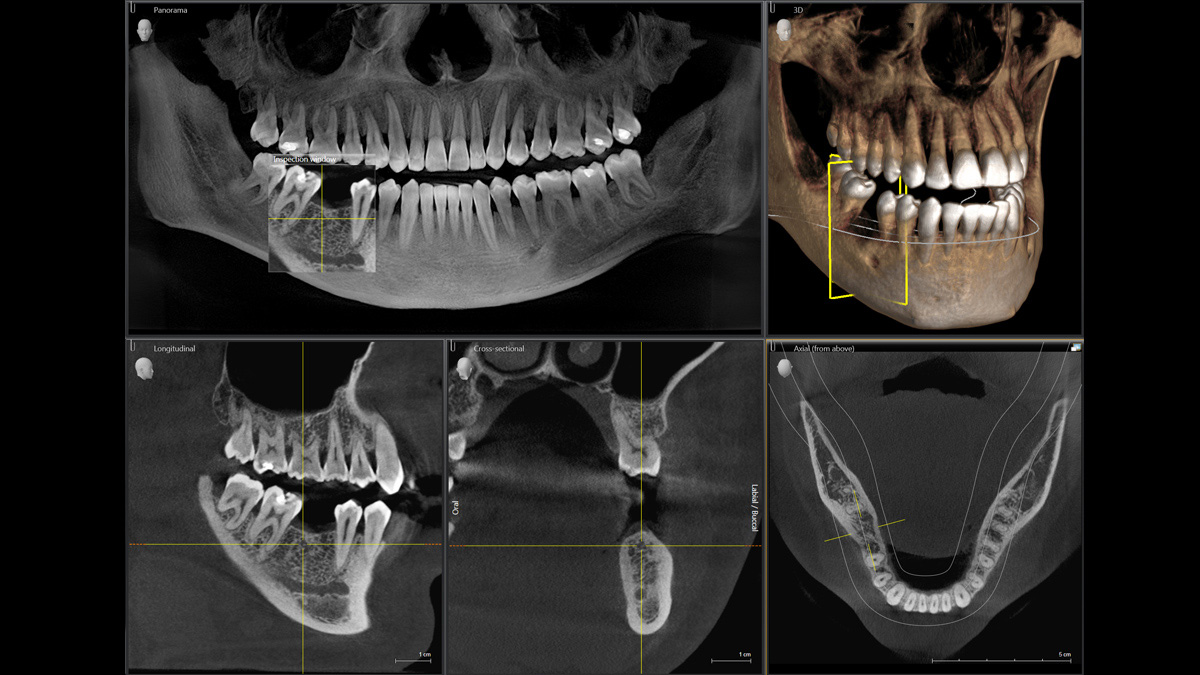

Der 2D/3D Power Performer Orthophos SL ist eine großartige Wahl für alle, die einfach mehr wollen. Der integrierte Direct Conversion Sensor (DCS) wurde für anspruchsvolle Bildqualitätsstandards entwickelt und bietet detaillierte Daten. Der intelligente Autofokus liefert automatisch fokussierte Panoramabilder mit hervorragender Gesamtschärfe. Orthophos SL bietet höchsten Bedienkomfort durch automatische Positionierung, eine anwenderfreundliche, intuitive Bedienung mit dem EasyPad und ein individuell einstellbares Umgebungslicht für ein exklusives Erscheinungsbild.

Mit dem Low Dose-Modus erhalten Sie 3D-Bilder im Dosisbereich einer 2D-Röntgenaufnahme. Im HD-Modus werden während eines einzelnen Umlaufs mehr als 800 Einzelbilder aufgenommen und zu einem 3D-Volumen mit bis zu 80 μm zusammengeführt. Der Vorteil für Sie: rauschärmere Aufnahmen in hoher Auflösung

Ein breites Spektrum an Volumengrößen für verschiedene diagnostische und klinische Anforderungen von Ø 5 × 5,5 cm bis Ø 11 × 10 cm